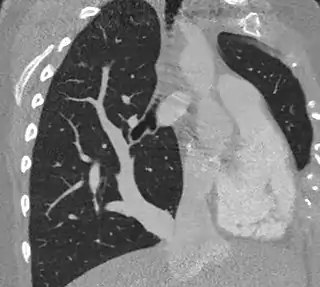

![]() Síndrome de la cimitarra.TAC torácico | ||

Así mismo, su imagen radiológica es clave, ya que recuerda a la de un sable turco en la radiografía de tórax simple. Suele estar acompañado por hipoplasia pulmonar derecha y dextrocardia. Su imagen radiológica corresponde a la visualización de un gran vaso venoso (drenaje de las venas pulmonares) anómalo que recorre la silueta cardíaca derecha para drenar en la vena cava inferior por arriba o por debajo del diafragma.